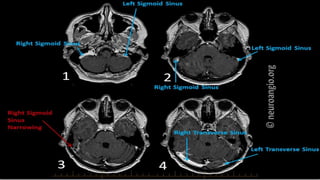

Blood supply

To quickly remember the tributaries to the confluence

of sinuses you can use the mnemonic

"TOSS"

(Transverse sinus, Occipital sinus, Superior sagittal sinus,

Straight sinus

Dural sinuses